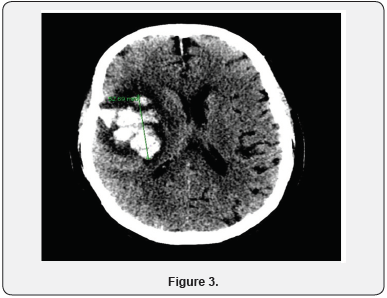

Initially patient was suspected to have meningitis and started on vancomycin, ampicillin, ceftriaxone and acyclovir. The antibiotics were stopped after HSV was confirmed and antiviral continued. On day 6 of hospitalization patient was noted to have decreased responsiveness. Patient had a Stat CT of the head which showed 5cm right temporal lobe hematoma with 3.5 mm midline shift to the Left (Figure 2). Neurosurgery was notified but it was determined that patient has a poor prognosis and is not a candidate for surgery. He was also transferred to intensive care due to respiratory distress and was intubated. The next day repeat CT of head showed increase in size of hematoma to 6 cm (Figure 3). Family decided to make the patient comfort care only and he was transferred to hospice.